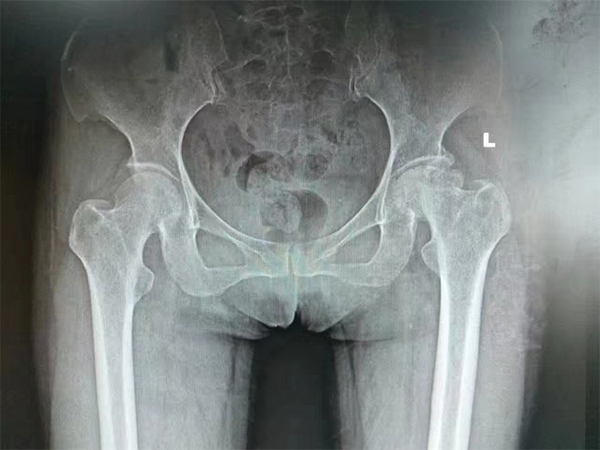

股骨头坏死

复位前后对比